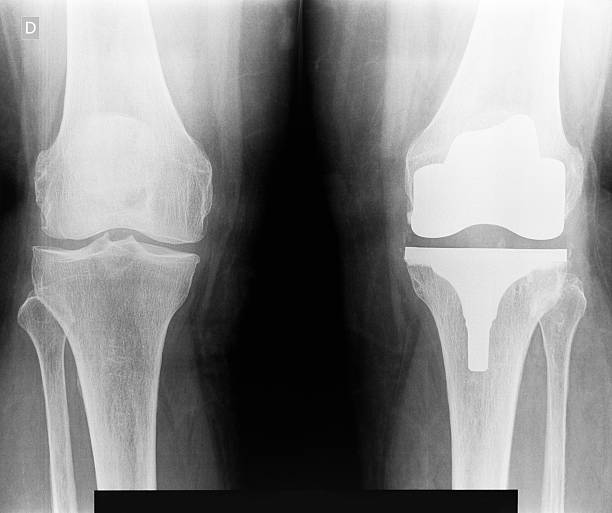

퇴행성 관절염은 특히 어르신들에게 삶의 질에 크게 영향을 줄 수 있습니다. 무릎 관절염으로 지속적인 통증에 시달리거나 경제적 이유로 수술을 받지 못하는 노인들의 고통을 경감하여 삶의 질을 개선하기 위해 의료비 지원사업이 시작되었습니다. 무릎 인공관절 수술 지원을 통해 60세 이상의 어르신들의 건강을 보장하고 의료비 부담을 경감해 들이기 위함이 이 사업의 목적 입니다. 무릎인공관절 지원사업에 대해 알아보고 선착순이니 빨리 신청하셔서 최대 120 만원의 수술비를 지원 받아 봅시다.

- 대상 질환 : 건강보험급여 '인공관절치환술(슬관절)' 인정기준에 준하는 질환자